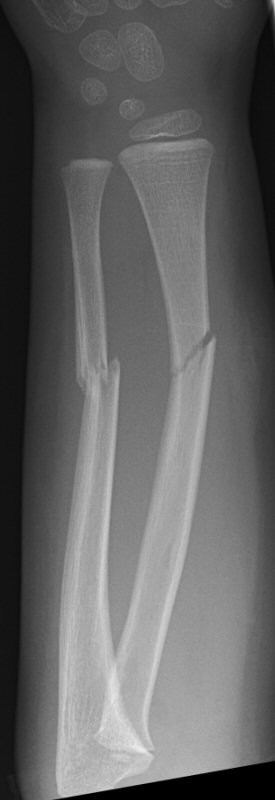

Exempel på rötngenbilder vid TEN-spikning:

Frontalbilder före och efter operation, resp. sidobilder före och efter operation med TEN-spikning i radius och ulna